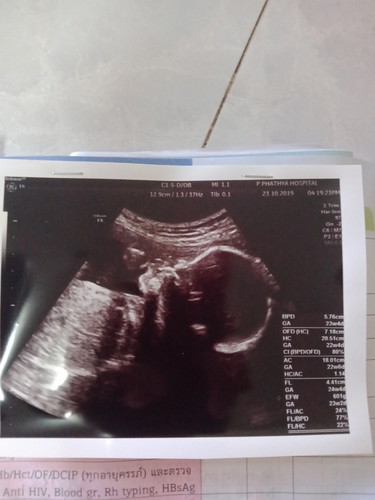

ใบซาวด์หัวน้องเป็นแบบนี้ถือว่าปกติไหมคะ ใครมีใบซาวด์ช่าวอายุครรภ์เท่าๆกัน ขอดูหน่อยคะ

ปกติค่ะ ตอน13วีค5วันค่ะ คางแหลมมาเชียว😂😂😂